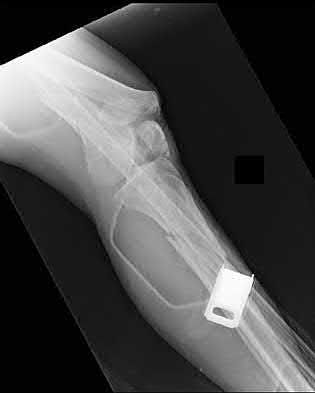

1. # A 32-year-old male sustains the injury shown in Figure A and undergoes treatment as shown in Figure B. Following placement of this implant, what is the best technique to confirm it is not too proud proximally?

1. Lateral radiograph of the knee

2. AP radiograph of the knee

3. Oblique radiographs of the knee

4. Merchant radiograph of the knee

5. Internally rotated 45 degree view of the knee Corrent answer: 1

The safe zone for tibial nail placement as seen on radiographs is just medial to the lateral tibial spine on the anteroposterior radiograph and immediately adjacent and anterior to the articular surface as visualized on the lateral radiograph.

Tornetta et al specifically located the safe zone for nail entry in a study using fresh frozen cadaver knees. The authors found that the safe zone for nail placement is located 9.1+/-5 millimeters lateral to the midline of the plateau and three millimeters lateral to the center of the tibial tubercle. The width of the safe zone averaged 22.9 millimeters and was as narrow as 12.6 millimeters.

The starting point of the of the nail can be best viewed on the lateral knee radiograph, an example of which is shown in Illustration A. Illustration B shows the "sweet spot" for nail insertion as defined by Tornetta.